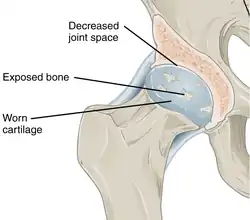

In a healthy joint, the ends of bones are encased in smooth cartilage. Together, they are protected by a joint capsule lined with a synovial membrane that produces synovial fluid. The capsule and fluid protect the cartilage, muscles, and connective tissues. -

With osteoarthritis, the cartilage becomes worn away. Spurs grow out from the edge of the bone, and synovial fluid increases. Altogether, the joint feels stiff and sore. -